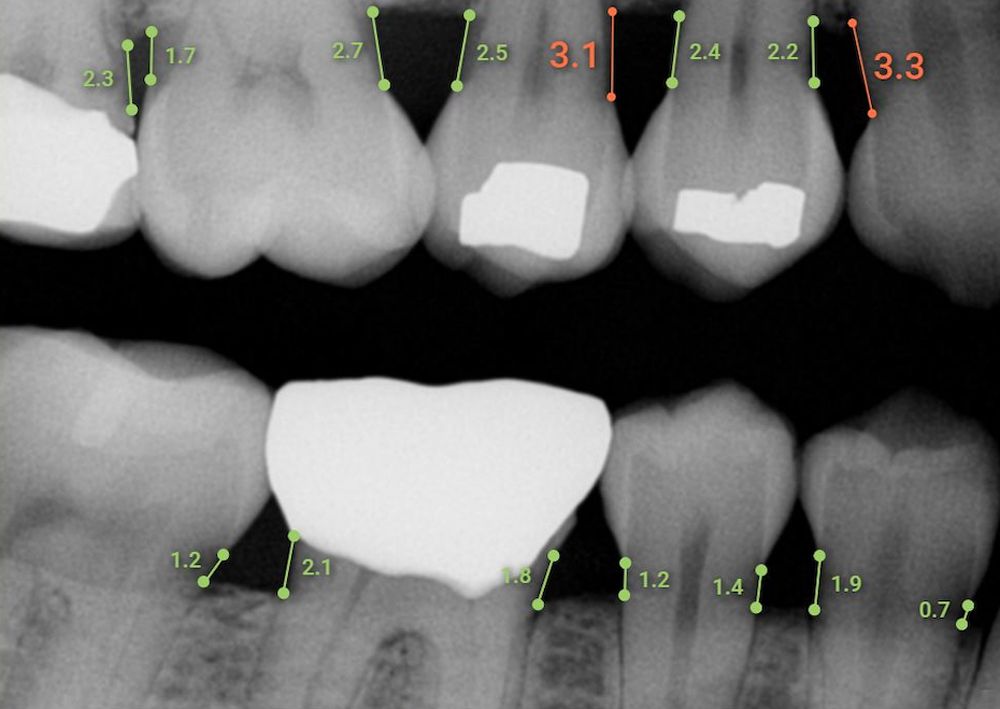

Overjet Dental Assist

Overjet’s Dental Assist™ applies artificial intelligence (AI) in real time to aid dentists and hygienists. It supports dental professionals in measuring mesial and distal bone levels in bitewing and periapical radiographs for the diagnosis and treatment planning of periodontal disease. In clinical performance testing, it demonstrated automated measurement capabilities comparable to those of a team of highly skilled dentists.